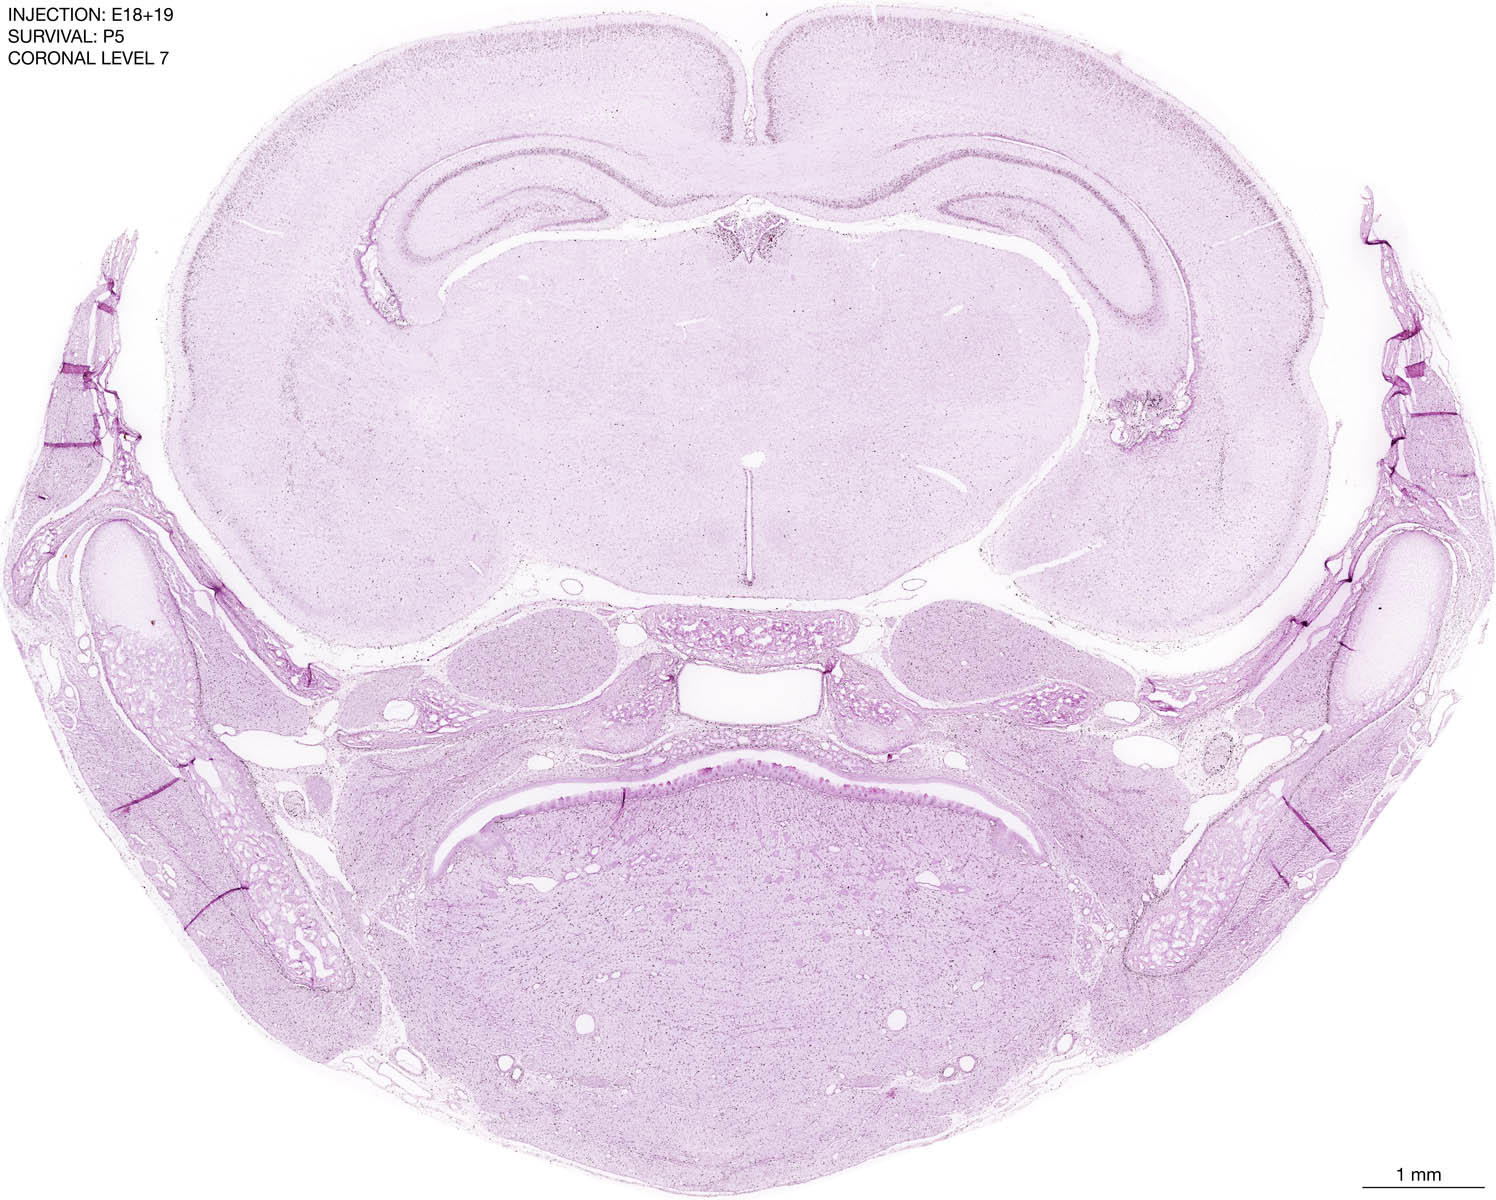

The images below are from the brain of a rat that was exposed to tritiated thymidine on E18+19 and survived to P5. Download: Large | High Res Download: Large | High Res Download: Large | High Res Download: Large | High Res Download: Large | High Res Download: Large | High Res Download: Large | High Res Download: Large | High Res Download: Large | High Res Download: Large | High Res Download: Large | High Res Download: Large | High Res Download: Large | High Res Download: Large | High Res Download: Large | High Res Download: Large | High Res Download: Large | High Res Download: Large | High Res Download: Large | High Res Download: Large | High Res Download: Large | High Res Download: Large | High Res Download: Large | High Res Download: Large | High Res